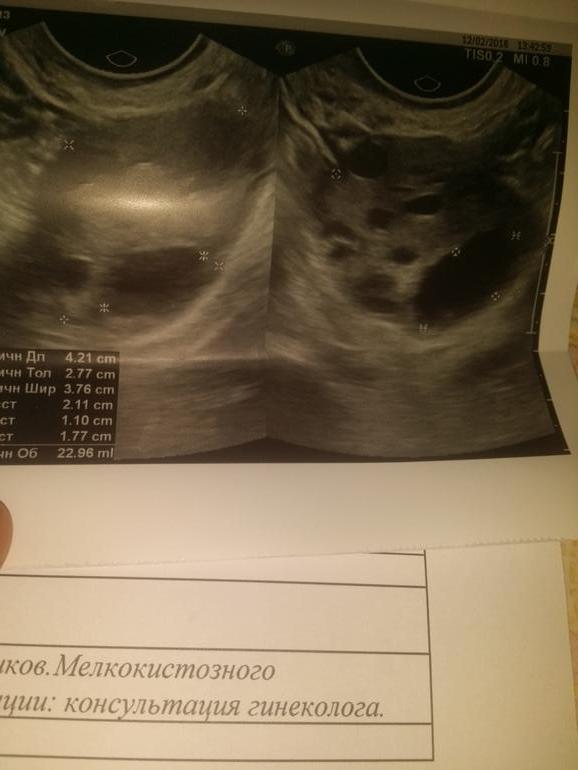

Задержка М и нет БДевочки,сос. Этот цикл нереально длинный.Более 40 дней.На 41 пошла на УЗИ,это было 12 февраля ..далее под кат врач попалась неудачная,ничего не сказала,вот дала заключение и бай-бай.С 5.02 по 11.02 была 1 капелька светлой крови каждое утро и только утром.

Исходя из УЗИ вообще неясно ,что в пя...жт,фолик,киста..но на след день обратила внимание на тт (строго с дня узи 37.2)и увеличилась грудь.думаю,что это все же фолик был и произошла о.кровь больше не приходила.

Прикрепляю фото узи и теста

Дополнила тест на беременность.Ну руки то чешутся.😄чист 😈вот такие чудеса)это получается фолликул так долго зрел?от 12 февраля он уже 21😮а темпа и грудь тогда блин от чего😐запуталась😯😄и когда теперь меськи то ждаааать😩